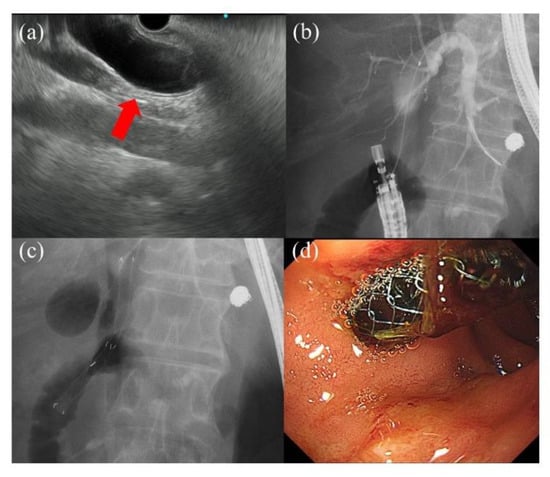

- Nakai, Y.; Sato, T.; Hakuta, R.; Ishigaki, K.; Saito, K.; Saito, T.; Takahara, N.; Hamada, T.; Mizuno, S.; Kogure, H.; et al. Long-term outcomes of a long, partially covered metal stent for EUS-guided hepaticogastrostomy in patients with malignant biliary obstruction (with video). Gastrointest. Endosc. 2020, 92, 623–631. [Google Scholar] [CrossRef] [PubMed]

- Iwashita, T.; Yasuda, I.; Doi, S.; Uemura, S.; Mabuchi, M.; Okuno, M.; Mukai, T.; Itoi, T.; Moriwaki, H. Endoscopic ultrasound-guided antegrade treatments for biliary disorders in patients with surgically altered anatomy. Dig. Dis. Sci. 2013, 58, 2417–2422. [Google Scholar] [CrossRef] [PubMed]

- Matsubara, S.; Nakagawa, K.; Suda, K.; Otsuka, T.; Isayama, H.; Nakai, Y.; Oka, M.; Nagoshi, S. A proposed algorithm for endoscopic ultrasound-guided rendezvous technique in failed biliary cannulation. J. Clin. Med. 2020, 9, 3879. [Google Scholar] [CrossRef] [PubMed]

- Hara, K.; Yamao, K.; Niwa, Y.; Sawaki, A.; Mizuno, N.; Hijioka, S.; Tajika, M.; Kawai, H.; Kondo, S.; Kobayashi, Y.; et al. Prospective clinical study of EUS-guided choledochoduodenostomy for malignant lower biliary tract obstruction. Am. J. Gastroenterol. 2011, 106, 1239–1245. [Google Scholar] [CrossRef]

- Song, T.J.; Hyun, Y.S.; Lee, S.S.; Park, D.H.; Seo, D.W.; Lee, S.K.; Kim, M.H. Endoscopic ultrasound-guided choledochoduodenostomies with fully covered self-expandable metallic stents. World J. Gastroenterol. 2012, 18, 4435–4440. [Google Scholar] [CrossRef]

- Kunda, R.; Pérez-Miranda, M.; Will, U.; Ullrich, S.; Brenke, D.; Dollhopf, M.; Meier, M.; Larghi, A. EUS-guided choledochoduodenostomy for malignant distal biliary obstruction using a lumen-apposing fully covered metal stent after failed ERCP. Surg. Endosc. 2016, 30, 5002–5008. [Google Scholar] [CrossRef]

- Lu, L.; Tang, X.; Jin, H.; Yang, J.; Zhang, X. Endoscopic ultrasound-guided biliary drainage using self-expandable metal stent for malignant biliary obstruction. Gastroenterol. Res. Pract. 2017, 2017, 6284094. [Google Scholar] [CrossRef]

- Dhindsa, B.S.; Mashiana, H.S.; Dhaliwal, A.; Mohan, B.P.; Jayaraj, M.; Sayles, H.; Singh, S.; Ohning, G.; Bhat, I.; Adler, D.G. EUS-guided biliary drainage: A systematic review and meta-analysis. Endosc. Ultrasound. 2020, 9, 101–109. [Google Scholar]